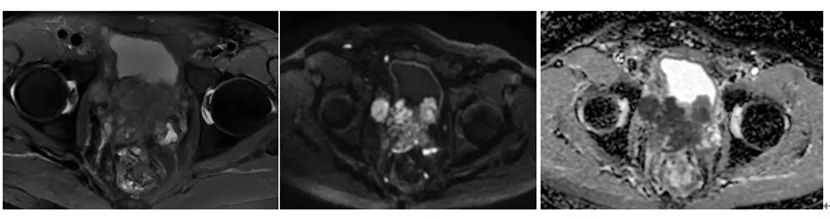

前列腺磁共振(2025-02-06)

前列腺体积增大,其内信号于T2-FS不均匀增高,DWI可见高信号;中央带增大为主,双侧外周带受压变扁,增强后前列腺可见明显不均匀强化。双侧盆壁见多发大小不等的结节影及肿块影,较大者最大截面约72mm×55mm。考虑前列腺癌,侵及膀胱,盆腔淋巴结转移、骨转移。